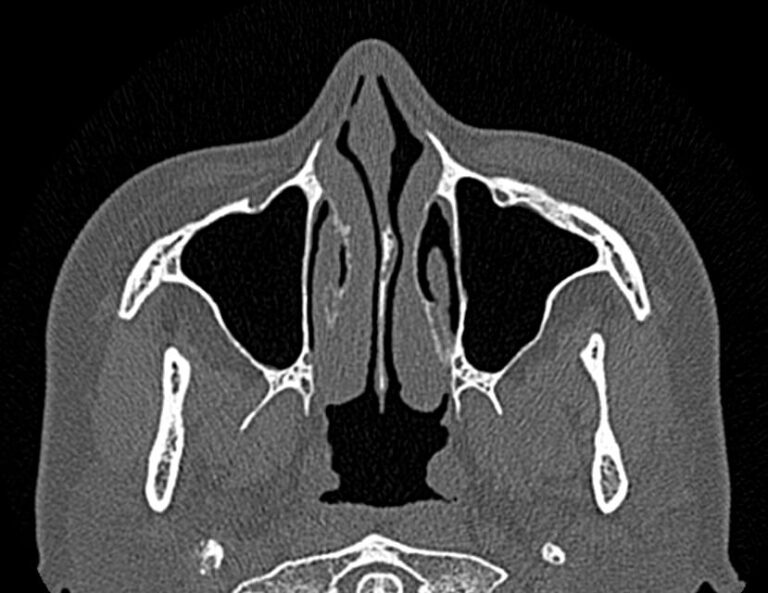

Золотым стандартом в диагностике патологических процессов пазух носа является мультиспиральная компьютерная томография, которая является быстрым безболезненным и неинвазивным (то есть без вмешательства в организм) способом исследования состояния синусов. Метод основан на проникающей способности ионизирующего излучения и получения изображений органов и тканей организма за счет разной степени поглощения ими рентгеновских лучей.

На основе полученных данных цифровые приложения томографов создают трехмерные реконструкции пазух носа, что позволяет оценить пространственное взаимоотношение анатомических структур и помогает в диагностике патологии околоносовых пазух.

Мультиспиральная компьютерная томография дает информацию о состоянии полости носа, носовой перегородки, степени воздушности околоносовых пазух, путей дренирования синусов, состоянии слезных каналов. Сканирование позволяет оценить толщину слизистой, наличие патологического содержимого в просвете пазух (уровня «жидкости»), выявить опухолевые образования. С помощью КТ можно провести точную диагностику травматических повреждений костей лицевого черепа, определить локализацию инородных тел, попавших в полости синусов.

С помощью объемной реконструкции можно перед оперативным вмешательством увидеть особенности анатомии ЛОР-органов, определить точное расположение патологического очага по отношению к окружающим тканям. Компьютерная томография помогает в диагностике аномалий развития придаточных пазух носа, слезоотводящих каналов.